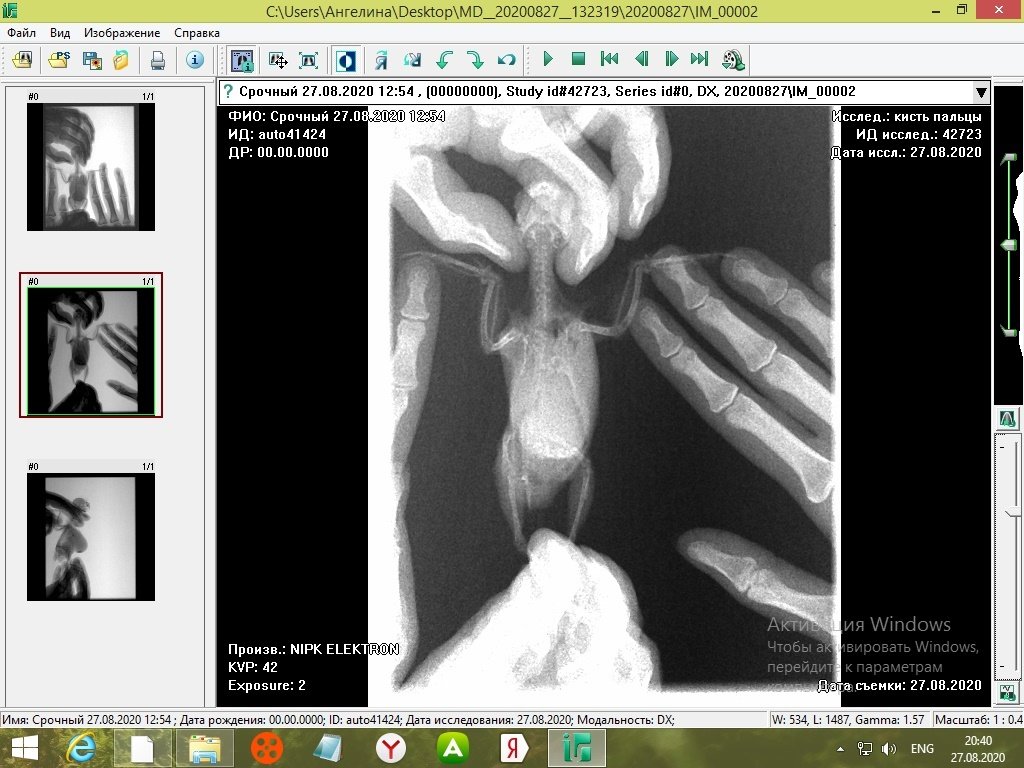

tanushka-sol2020 Опубликовано 27 августа, 2020 Автор #15 Опубликовано 27 августа, 2020 Некадрированные исходные снимки --- щёлкните полосу ниже. Скрытый текст

Кузяныч Опубликовано 28 августа, 2020 #16 Опубликовано 28 августа, 2020 Ох, бедная волнушка... В помёте на шли бактерии (++), слизь (+), жир (+), клетчатку (++)... Есть и непонятные для меня записи... По рентгену на втором снимке справа мне видится что эта огромная припухлость --- растянутый зоб... 18.08.2020 в 17:16, tanushka-sol2020 сказал: Что за опухоль? Она в моих руках меняется: то сморщится, то раздувается как шар надувной... Неужели, действительно зоб?... @tanushka-sol2020, срочно звоните Зосе, просите посмотреть снимки. Мазок из клюва... уф-ф... не знаю пока на сколько он нужен... Если на нистатине птице легче, то давайте его --- придерживайтесь дозировок, что давала вам Зося. Расположите лесенку горизонтально чтоб попугайчик экономил силы. Установите всё как можно ниже к полу. Проверьте, чтоб птичка не пыталась лезть выше и не висла на стенке. Помёт оранжевый... возможно, действительно, печень страдает... Карсил не отменяйте... За гепатовет и как вообще быть я не могу сказать. Нужно чтоб Зося посмотрела рентген. Свяжитесь, пожалуйста, с ней. У меня такое впечатление, что у этой волнушки растянут зоб и от этого плохо уходит и застаивается, протухая, пища.

tanushka-sol2020 Опубликовано 28 августа, 2020 Автор #17 Опубликовано 28 августа, 2020 (изменено) @Кузяныч К сожалению, от нистатина у нее сильно страдает печень. Я не стала ей давать, почти 3 недели принимали. Но срыгивание снова вернулось. Когда я собирала мазок из глотки, она потом срыгнула на одежду. Капли были песочного цвета и консистенция, как каша жиденькая. Но с запахом. Переживаю, вдруг неправильно сделала мазок, впервые же. Во вторнике будет готов анализ. Отпишусь. Рентген делали в больнице, я их кое-как уговорила. Первый "блин с комом", тоже выложила. Вдруг качества нет на снимке, что показал. Завтра Зосе позвоню. Спасибо, что ответили. Эти снимки неудачные выше, племянница скидывала. Я немного контраст отрегулировала, чтобы было видно. Изменено 28 августа, 2020 пользователем tanushka-sol2020

Zosia Опубликовано 30 августа, 2020 #23 Опубликовано 30 августа, 2020 Автор, вы самодеятельно изменили дозировку нистатина птице. Тем амым вы вырастили резистентную к нистатину грибковую флору. Так что теперь вам придется покупать Амфотерицин В. И Гептрал.скорее всего. Как купите- напишите что и в какой дозе купили. Далее. наконец перо на груди и зобу птицы, отчешите его- и сфотографируйте тот кошмар,который под пером прячется. По форме это- не липома.Точнее так- сейчас не липома. Далее. Прощупайте "мешок" зоба тщательно, натощак, пытаясь ощутить- есть ли между противопоставленными стенками зоба "лишнеяя" ткань. Если есть- то какая- плотная, дольчатая.цельная, четко отграниченная или нет. На дней того,что находится на месте зоба- я вижу конкременты. Не давать птице никаких камушков и песка! Учитывая вес объекта и вес птицы- она на самом деле весит едва 30 граммов. Обогрев- круглосуточный. Корма- самые любимые. По уму- зоб вскрывать и смотреть что внутри. Прогноз- отрицательный..